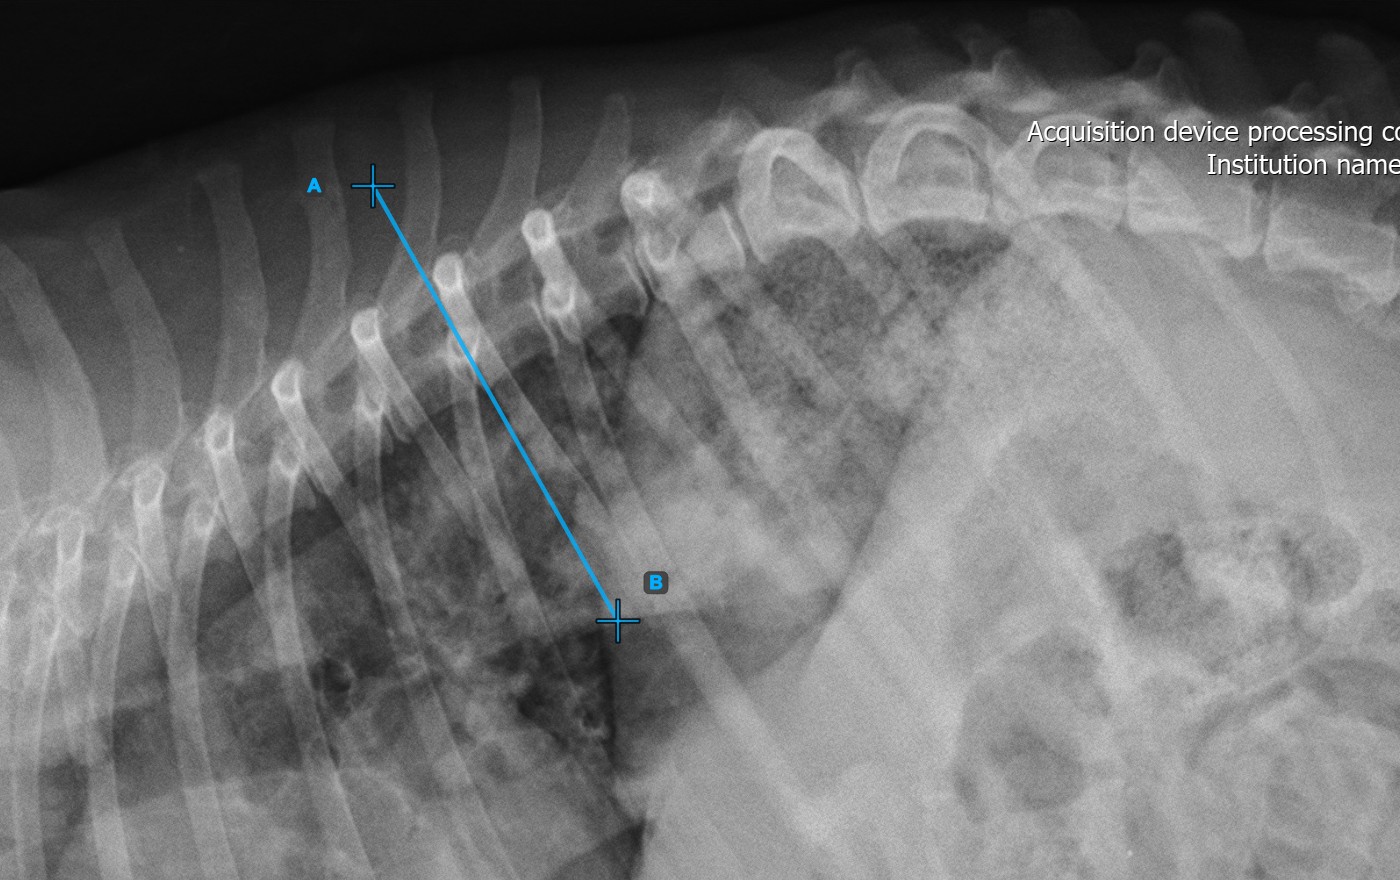

The image below represents a typical placement of the second vertebral line.

Modify the position and orientation of the two vertebral lines to automatically recalculate the Cobb Angle.